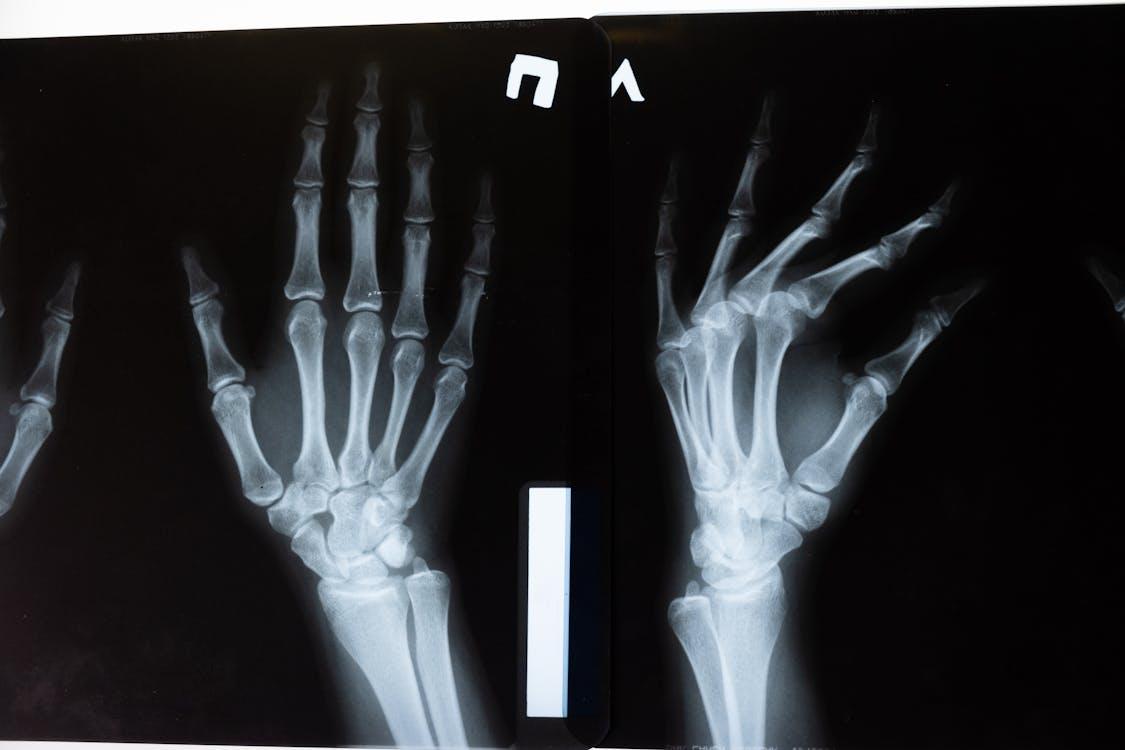

The musculoskeletal system is an intricate network of bones, muscles, joints, tendons, and ligaments. They work in perfect harmony to allow for movement. When one piece of this puzzle is slightly out of alignment, the entire system feels the strain. A “minor” issue, such as a grade one strain or mild tendonitis, might not seem like a cause for alarm, but it changes the way you move.

• Decreased Grip Strength: Struggling to open jars or hold a pen for long periods.